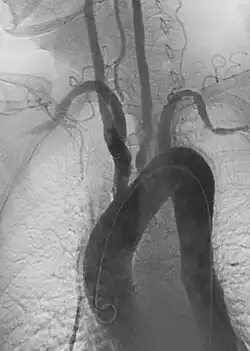

• Endovascular aneurysm repair: Placement of endovascular stent-graft across an aneurysm to prevent expansion or progression of the defective vessel.[6]

1. Aortic aneurysms include thoracic, abdominal and thoracoabdominal aneurysms. Treatment strategies are customized depending on the location, size, rate of growth and extent of the aneurysm as well as the medical comorbidities of the patient. For example, an intact, small but slowly growing aneurysm may be safely monitored with serial imaging for months or years before elective repair is considered. Elective endovascular aortic grafting is now routinely attempted when possible. Endovascular aortic repair (EVAR) refers to treatment of an abdominal aortic aneurysm, while thoracic endovascular aortic repair (TEVAR) is performed on the thoracic aorta. A ruptured aneurysm may be taken emergently for open, endovascular or combination repair.

A variety of endovascular grafts are available, and each has advantages and disadvantages depending on the characteristics of the aneurysm and patient.[90]